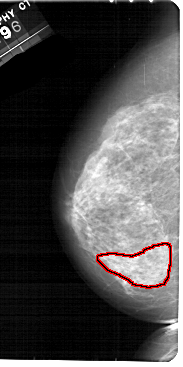

FILE: A_1885_1.LEFT_CC.OVERLAY

TOTAL_ABNORMALITIES 1

ABNORMALITY 1

LESION_TYPE CALCIFICATION TYPE PLEOMORPHIC DISTRIBUTION SEGMENTAL

ASSESSMENT 4

SUBTLETY 2

PATHOLOGY BENIGN

TOTAL_OUTLINES 1

BOUNDARY

LEFT_CC LINES 5491 PIXELS_PER_LINE 2731 BITS_PER_PIXEL 12 RESOLUTION 43.5 OVERLAY